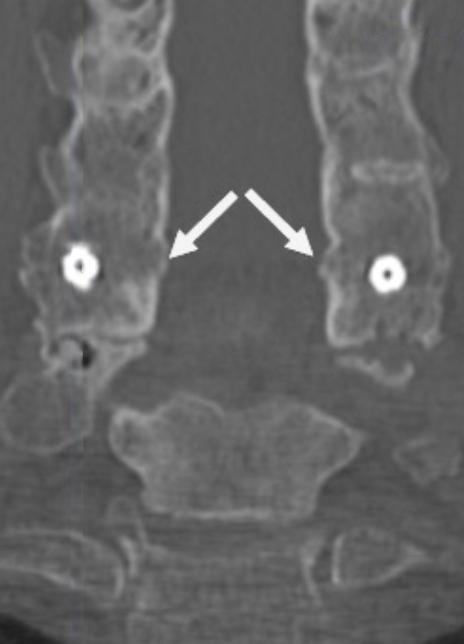

Coronal CT image showing circumferential bone bridging around the ION-C implants bilaterally.